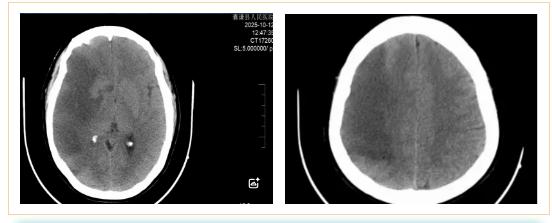

2025年10月11日,42岁的女性患者因突发左侧肢体无力、呕吐、意识障碍等症状被紧急送医。医院立即开启绿色通道,迅速完成头颅MRI检查,并在黄金时间窗内实施了阿替普酶静脉溶栓治疗。次日,患者病情急剧恶化,出现严重脑水肿并形成脑疝。虽曾考虑转往西宁进一步救治,但因路途遥远、转运风险巨大,加之患者家属对医院充满信任,最终决定留在囊谦县人民医院继续治疗。

在医疗条件相对有限的高原县城,救治团队克服困难,对患者进行了不间断的严密监测,连续追踪头颅CT影像变化。经过数个日夜的坚守和精心治疗,患者的病情终于出现了转机。至10月22日复查显示,致命的脑疝得到缓解,脑水肿范围显著缩小,患者成功度过了最危险的阶段,病情逐步稳定下来。